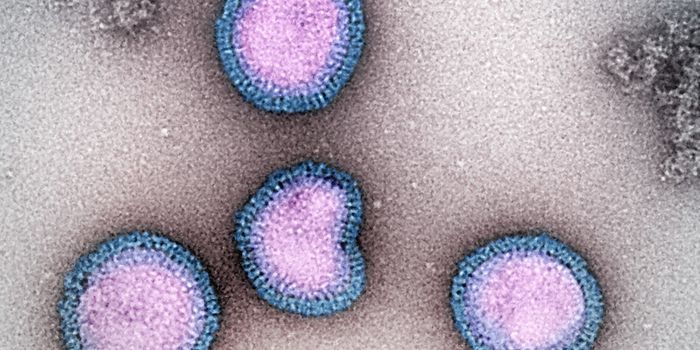

FEB 03, 2025MicrobiologyThe highly pathogenic avian influenza H5N1 infection has killed millions of birds around the world, and has spread to hu ...

NOV 24, 2024Clinical & Molecular DXAvian flu, particularly the highly pathogenic avian influenza H5N1, have caused huge amounts of wild and agricultural bi ...

NOV 15, 2024MicrobiologyThere are many processes and proteins that help the body fight a flu infection. One of them is known as IFITM3.